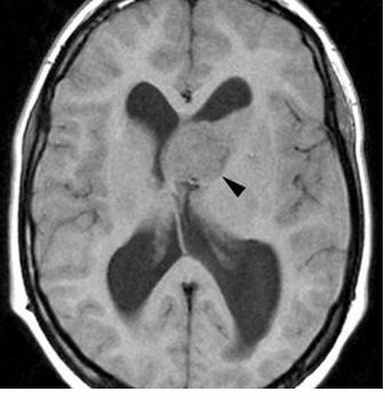

Анапластические астроцитомы похожи на астроцитомы низкой степени злокачественности, но более вариабельны в своих проявлениях, и опухоль может демонстрировать высокую гетерогенность.

Ключом к отличию анапластических астроцитом от опухолей низкой степени злокачественности является накопление контрастного вещества, которое должно отсутствовать в последних (хотя следует отметить, что некоторые типы опухолей, особенно гемистоцитарные астроцитомы, могут демонстрировать контрастное усиление). Паттерны контрастного усиления очень вариабельны [1].

В отличие от глиобластом, для анапластической астроцитомы характерно отсутствие выраженного некроза, соответственно, центрально расположенные области, не накапливающие контрастное вещество, по своим сигнальным характеристикам соответствующие жидкости, должны отсутствовать.

- Т1: гипоинтесивные по отношению к белому веществу

- Т2: гиперинтенсивные, но могут быть гетерогенные в случае наличия продуктов распада крови

- Т1 с парамагнетиками

- очень варьирует, однако, имеет место накопление контрастного вещества

- наличие кольцевидного накопления контрастного усиления характерно глиобластоме, а не АА